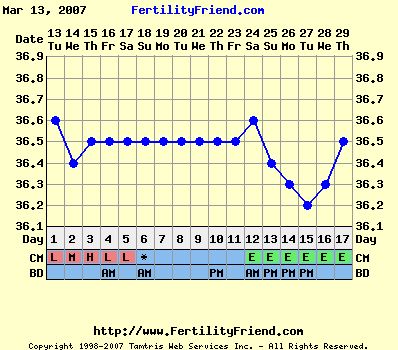

annyira átérzem a helyzeted! De a hőd középidőben mászott lefelé, és most elkezdett fölfelé... Ez jóóóóóó!!! És ti megtettetek mindent, úgyhogy tényleg nyugi. A párod meg egy tünemény! Szerintem ha megkérnéd, hogy maradjon otthon veled és tartsa a lábadat egész nap gyertyában, azt is megtenné!